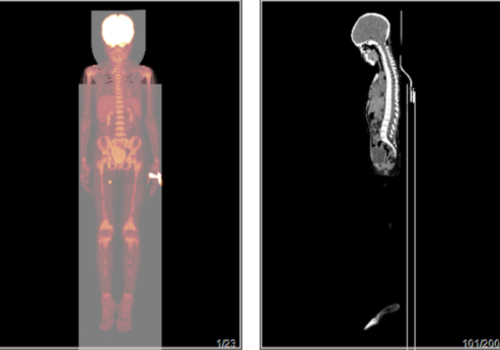

简要病史:左下肢酸痛数年,偶有麻木,近3天加重。偶有心前区疼痛。现拟行PETCT排除恶性病变。无进食;无手术史;无结核史;无外伤史;无糖尿病史;无肝炎史;无传染病史;无其他疾病史;有吸烟史,吸烟五十余年,每日一包;有饮酒史,饮酒二十余年,黄酒350g;无家族史;意识:清楚;空腹血糖:5. 4 mmol/L;诊断结果:1.全身(包括脑)PET显像未见FDG代谢明显异常增高灶。2.右额颅骨内板下高密度影,未见FDG代谢异常增高,考虑良性,访;副鼻窦炎。3.左肺上叶良性结节;双肺少许慢性炎症;冠脉钙化灶。4.食道下段炎、十二指肠球炎、结直肠炎,必要时内镜随访。5.肝脏嚢肿;左肾嚢肿;腹膜后及肠系膜淋巴结炎性增生。6.前列腺增生、FDG代谢轻度增高,建议PSA、fPSA随访。7.颈胸腰椎体骨质增生;腰2/3、腰3/4椎间盘膨出。